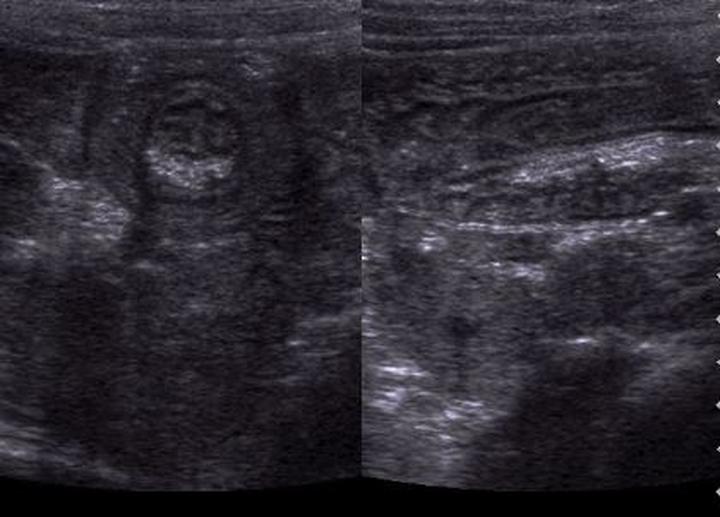

Ultrasonografia, znana w skrócie jako USG, stanowi jedno z badań, które od razu przychodzi na myśl, gdy rozważamy diagnostykę medyczną. Warto jednak zauważyć, że kiedy mówimy o wykrywaniu nowotworów, szczególnie raka jelita grubego, USG nie pokazuje pełni swoich możliwości. Ma swoje ograniczenia, zwłaszcza w przypadku małych zmian, a diagnostyka wczesnych stadiów nowotworów nie zagwarantuje najlepszych wyników. Możemy porównać USG do dobrego kucharza, który przyrządza znakomity obiad, ale zapomniał o soli – wszyscy odczuwają, że czegoś brakuje, ale nikt nie potrafi dokładnie zidentyfikować problemu.

W dodatku obrazowanie ultrasonograficzne charakteryzuje się szczególnymi cechami. Z łatwością wykrywa duże guzy, które mogłyby nawet zabierać głos w karaoke, natomiast rozpoznawanie subtelnych, małych zmian, które mogą w przyszłości przekształcić się w nowotwory, sprawia jej trudności. Dlatego poleganie wyłącznie na USG w kontekście wykrywania raka jelita grubego przypomina kupowanie losu na loterii – lepiej mieć różne metody w zasięgu ręki, aby zwiększyć swoje szanse na sukces. Warto więc rozważyć takie alternatywy, jak kolonoskopy, tomografy komputerowe czy rezonanse magnetyczne, które dostarczają znacznie więcej informacji niż wywiad w programie plotkarskim.

Ciekawostką jest, że z badania ultrasonograficznego korzysta się nie tylko w diagnostyce nowotworów, ale także w prenatalnej ocenie zdrowia płodu, co pokazuje wszechstronność tej technologii, mimo jej ograniczeń w wykrywaniu zmian nowotworowych w jelicie grubym.